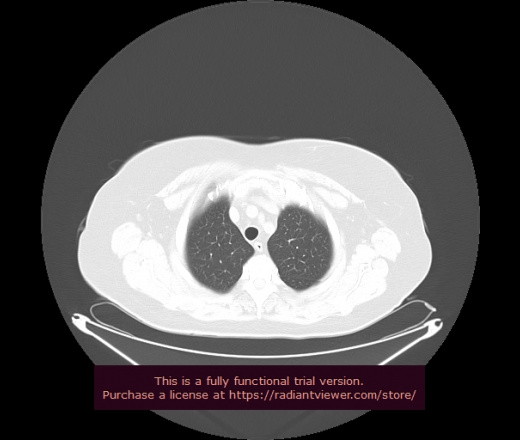

Уважаемые коллеги, если имеется интерес, сможете ли Вы спрогнозировать дальнейшее +-одинаковое течение процесса у 4 данных разных пациентов? Зацепиться где-то можно очень просто, где-то нельзя.